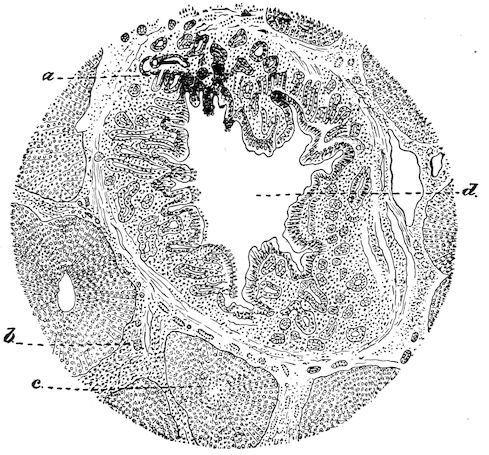

114. The fourth phase, or period of osteomalacia, i.e. softening of the bones, is also the last. It is rarely seen in large animals like horses and oxen, because accidents so often accompany the preceding stages and necessitate slaughter; but it is common in goats and pigs.

In this phase the bones become elastic, soft and depressible, yielding to the pressure of the operator’s fingers.

The flat bones are particularly liable to this change, which is common to domesticated animals. The bones of the head are the first to suffer; later those of the pelvis. The lower jaw becomes swollen, particularly about the centre of the branches which may attain three, four, or five times, their normal thickness.

The depression in the submaxillary space disappears. The upper jaw undergoes similar changes, becoming deformed and thickened until the cavities of the sinuses and the hollow appearance of the palate are lost, while the face is so changed that it cannot be recognised as that of a horse, goat, etc.

The molar teeth are almost buried, their tables alone being visible at the bottom of a depression, the edges of which rise above the neighbouring parts (pig).

Mastication is clearly impossible, the jaws appear paralysed, the muscles powerless, and only swallowing is possible, a fact which explains why life is only prolonged to this stage in animals which can be fed with a spoon or bottle (pigs and goats). The bones of the cranium, although greatly changed in texture, are always less deformed than those of the face.

The changes are such that it is often easy with a mere post-mortem knife to cut the head completely in two. Osseous tissue, properly so-called, has disappeared.

All the constituent tissues, with the exception of the skin and muscles, i.e., the bone, periosteum and aponeuroses, have the appearance and consistence on section of the fibro-lardaceous tissue seen in chronic inflammation.

Lesions. The chief lesions are to be found in the bones. They consist in rarefaction of the compact tissue, increase in size of the medullary cavity and Haversian canals, and enlargement of the areolæ of the spongy tissue. The bone marrow loses its fatty constituents, appears red and gelatinous, and contains a greatly exaggerated number of blood-vessels. When heated, the bones do not yield oil as in healthy subjects, and when dry, they seem abnormally porous. In the osteoclastic phase, the bones become very friable and even the shafts assume 17a spongy appearance. They diminish in density. These changes correspond to the stages of eccentric rarefying ostitis and osteoporosis of German authors.

The flat bones often show well-marked periostitis, but the great thickening sometimes seen in certain of the bones of the head appears to be the result of a special osteo-periostitis. It is quite certain that the disease is due to something more than a mere want of mineral constituents in the bone, and poverty in this respect certainly does not explain the hypertrophic changes. The nutrition of the bones as a whole is disturbed, resulting in alterations both in the ossein and in the mineral salts, the whole process being accompanied by symptoms of osteo-periostitis.

Fig. 8.—Transverse section through the middle region of the face in a pig suffering from osseous cachexia.

18In the final stages, the bones may be cut with a knife, and a time arrives when bony tissue seems completely to have disappeared; thus, as shown in Fig. 8 herewith, it was possible to cut the entire head of a pig into thin slices without the slightest difficulty. All parts of the head had been affected by the softening change.

From the chemical point of view, the diminution in mineral salts and in phosphate of calcium has long been recognised, but the degree of this change varies according to the phase. In human beings the proportions have been estimated as follows: Normal bone, 50 to 80 per cent. of phosphate of calcium; bone in persons suffering from osteomalacia, 5 to 20 per cent. of phosphate of calcium. The changes in the ossein have not been carefully studied. We only know that histologically the ossein becomes fibrillar, and that chemically it no longer retains its normal composition.